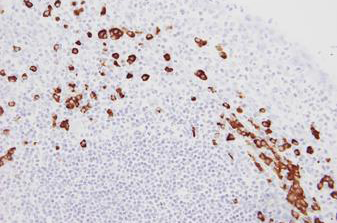

Human tonsil: in situ hybridization for kappa mRNA using Kappa Probe, Anti-Fluorescein Antibody and BOND Polymer Refine Detection.

Kappa Probe is used for the qualitative identification of Kappa light chain messenger RNA (mRNA) in formalin-fixed, paraffin-embedded tissue by in situ hybridization (ISH) using the automated BOND system.